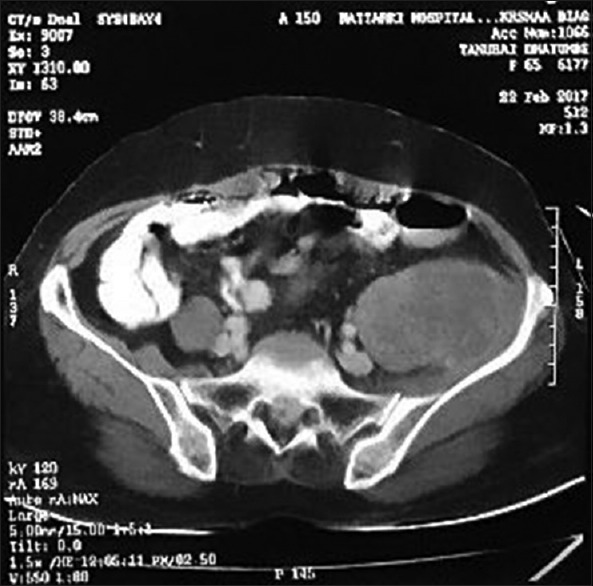

A 65-year-old female patient presented with the chief complaints of pain in the left iliac fossa (LIF) radiating to the left thigh for the past 2 months. Initially, she could carry out her routine work with a performance status (Eastern Cooperative Oncology Group) of 1 which worsened to a status of 2 as the pain intensified to be spasmodic. There was no history of bleeding per rectum, constipation. On clinical examination, a mass-like sensation which was felt after deep palpation in the LIF. Due to the adhesive mass, there was a flexion deformity with inhibition of hip extension. The flexion deformity gradually increased over 2 months with complete loss of extension [Figure 1]. A provisional diagnosis of an abdominal lump in the LIF was made. On palpation, there was tenderness, mass felt smooth, firm, and afebrile. Application of Thomas test helped me define the exact flexion deformity, which was around 40°–45°. She was evaluated with computed tomography (CT) scan of the abdomen and the pelvis which showed a large well defined soft tissue density mildly enhancing lesion in LIF involving the psoas and iliac muscles and extending to the inguinal region of the size: 11.3 cm × 7.4 cm × 5.8 cm [Figure 2]. There were calcific foci within the mass. A confirmatory histopathological examination represented a mass showing diffuse undifferentiated sarcoma cells. Thus, the diagnosis of the tumor was pleomorphic RMS with a pathological staging of pT2 N0 M0. Complete surgical resection of the main tumor, along with some surrounding normal tissue of the iliopsoas was achieved [Figure 3].

| Figure 2:There is a mass present retroperitoneally on the left side in the area of iliacus and psoas muscle (T12–L1)